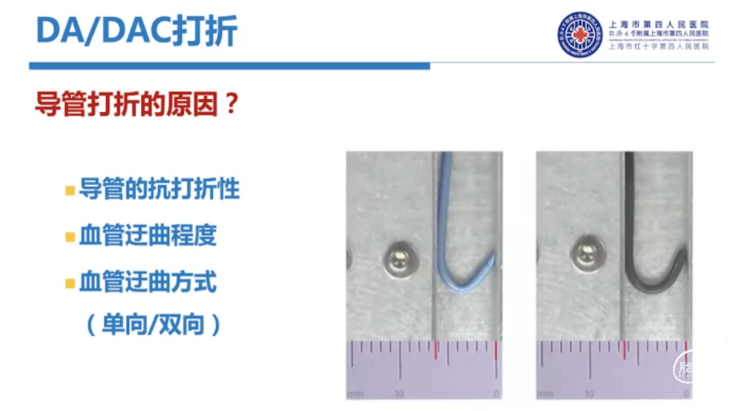

导管是否打折,和转弯半径有很大关系。一方面取决于导管性能,一方面取决于血管条件。在没有足够支撑情况下,导管非常容易形成锐角,这个时候就容易打折。目前可以通过加硬导丝增加内支撑,让血管在弯的位置更多地靠在大弯一侧,来增加它的半径,进一步减少打折情况的出现。